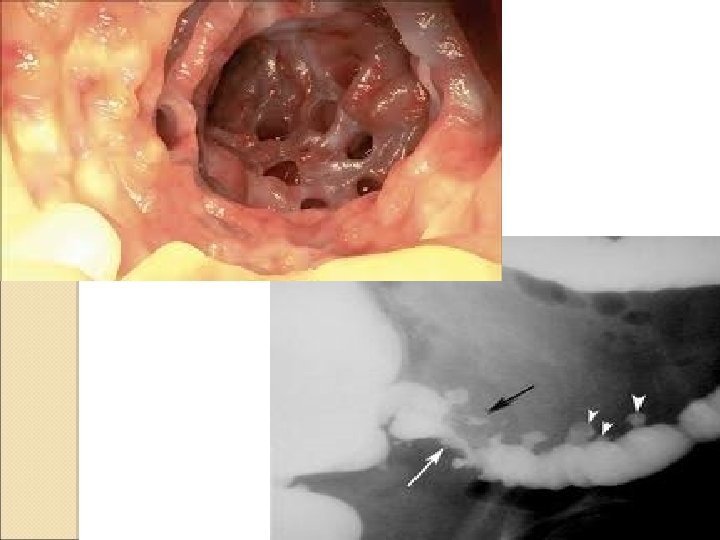

Julio: �Comienza nuevamente con dolor en hemiabdomen izquierdo. �Se le realiza SOH con resultado positivo �Colonoscopia: Colonoscopia Sigma con numerosos divertículos con mucosa intensamente inflamatoria y secreción mucopurulenta sugestiva de diverticulitis. �Eco abdominal: abdominal Engrosamiento de la pared de sigma con hiperecogenicidad de grasa pericólica. No se aprecian colecciones pericólicas